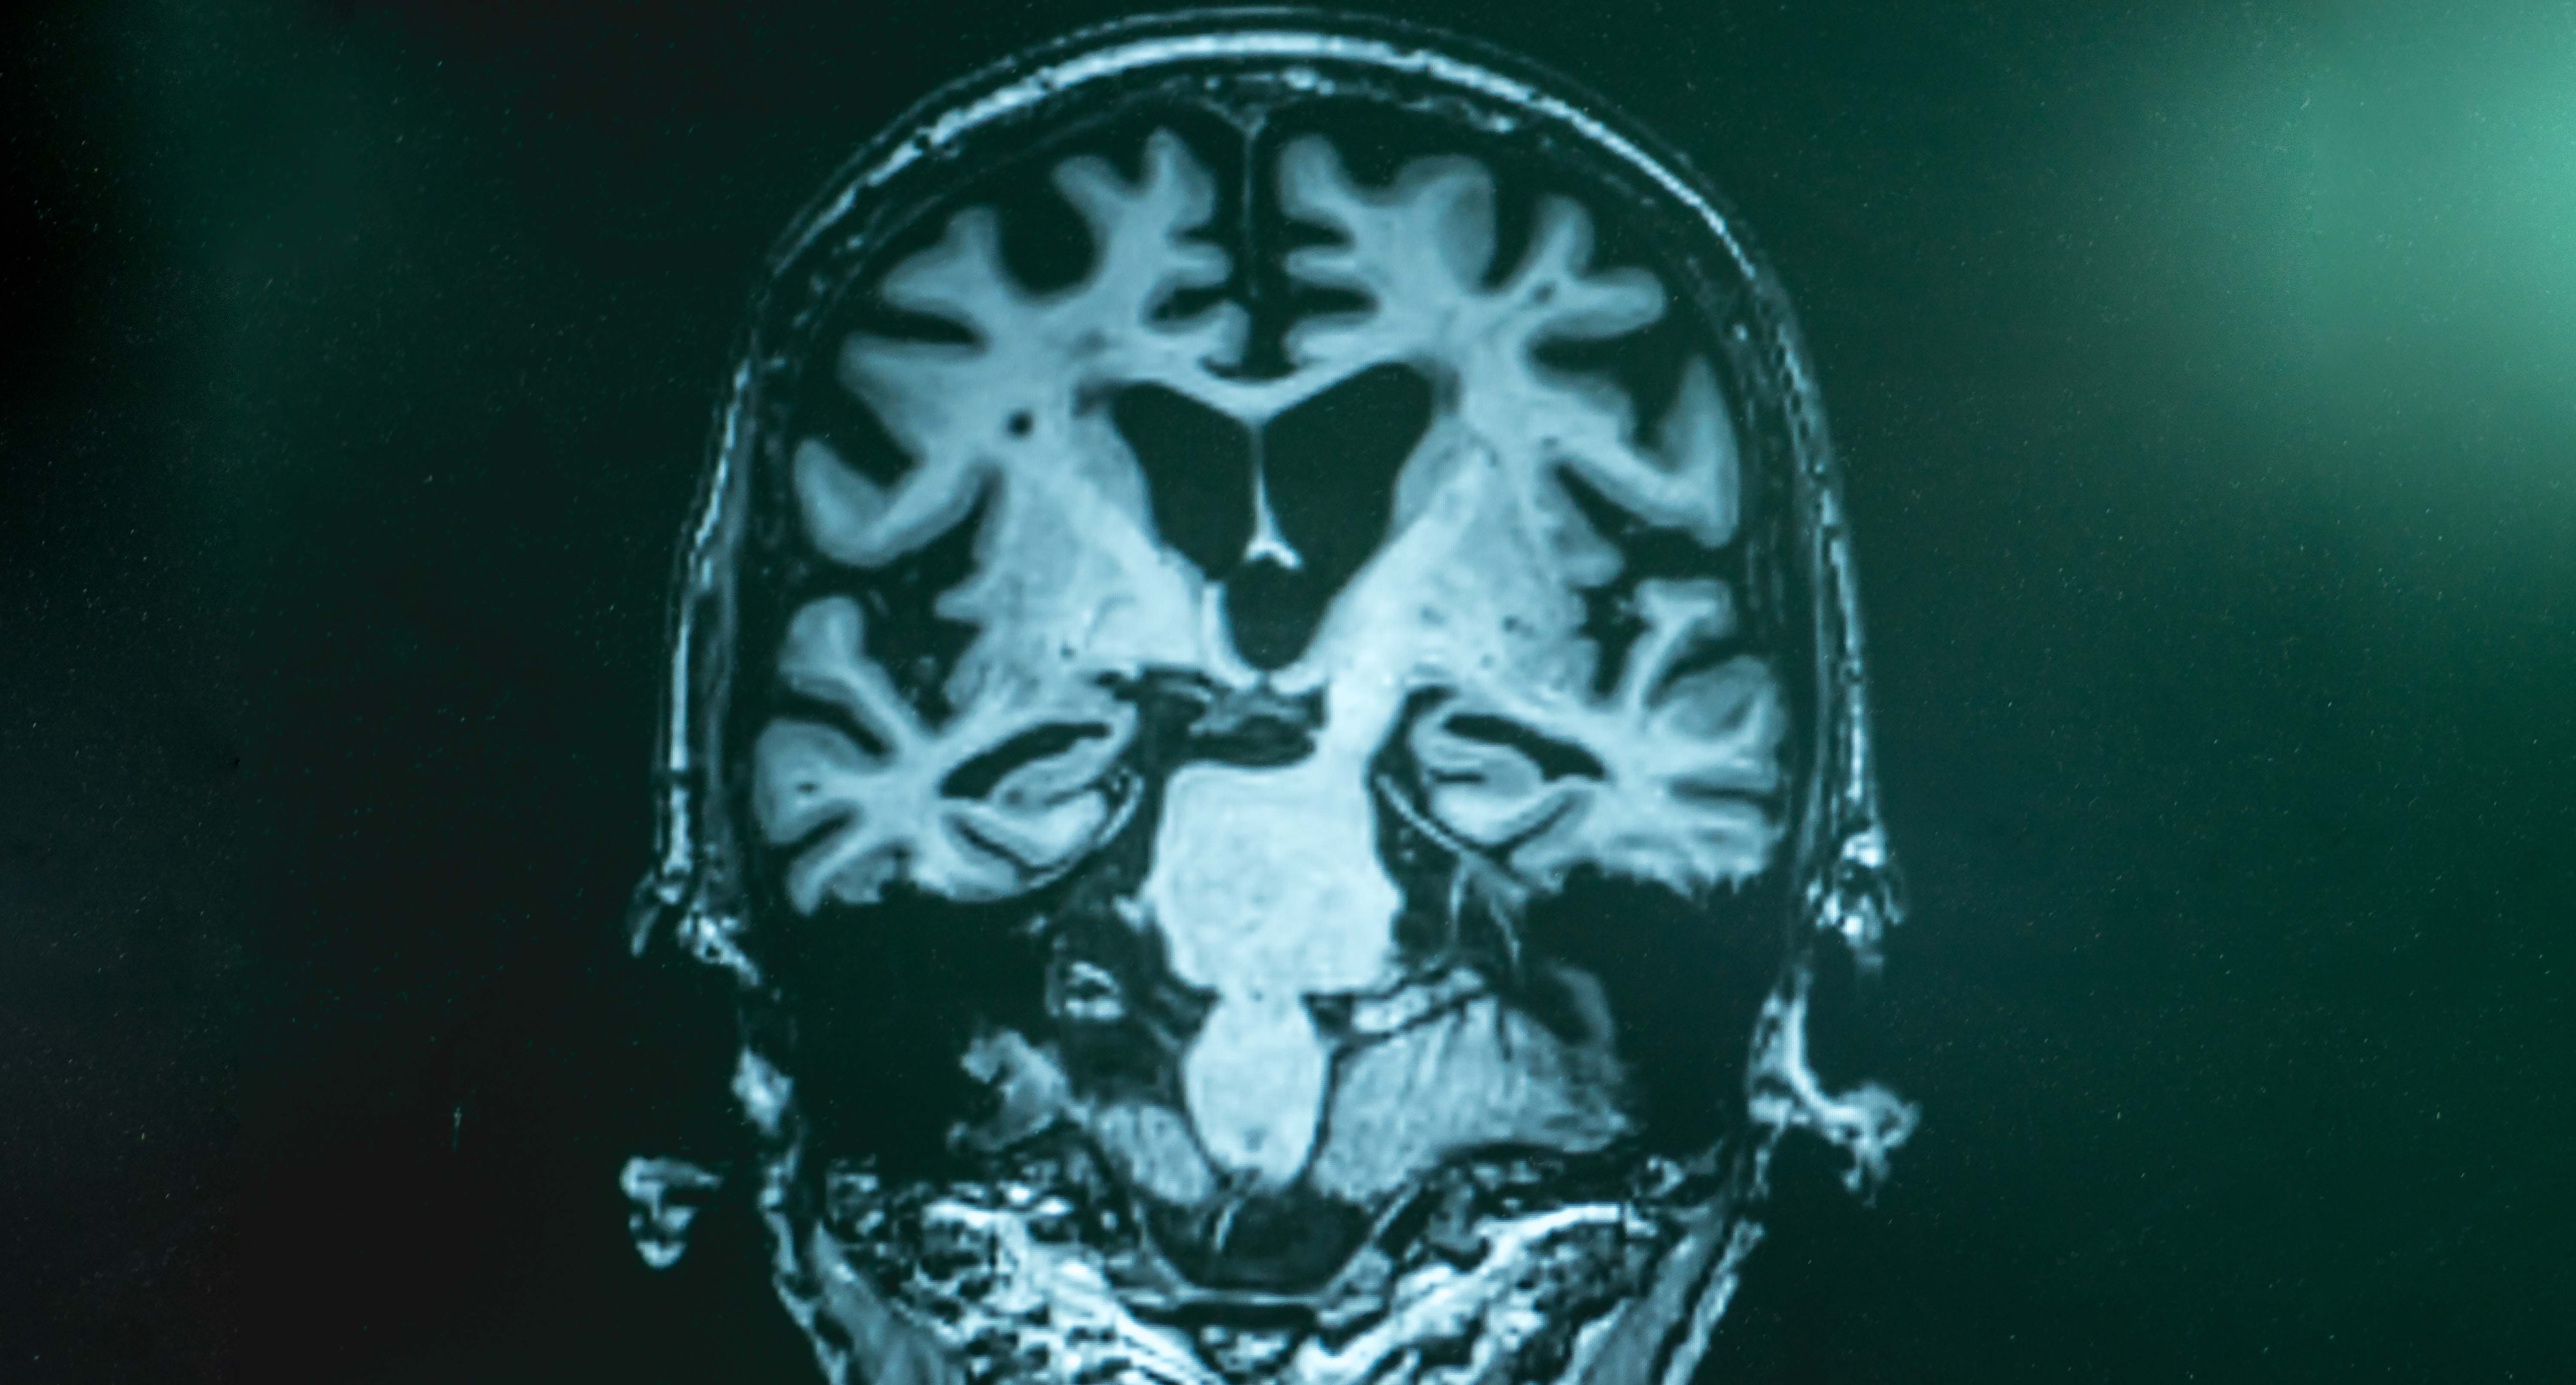

BARCELONA, España – Un equipo internacional liderado por investigadores de la Fundación española Pasqual Maragall ha corroborado, en un estudio con una amplia cohorte y biomarcadores, la relación entre mala calidad del sueño y un mayor riesgo de desarrollar alzhéimer en personas sin deterioro cognitivo.

Los resultados del análisis, liderado por el Barcelonaβeta Brain Research Center (BBRC) de la Fundación Pasqual Maragall, se han publicado en la revista científica Brain Communications y pueden ser relevantes para ayudar a definir futuras terapias.

Para este estudio, hecho público este jueves, se ha empleado la cohorte más grande hasta la fecha (el estudio europeo de cohortes longitudinales para prevención de la demencia por alzhéimer) y se han añadido unos biomarcadores de líquido cefalorraquídeo, que predicen incrementos futuros de la patología en personas sin síntomas identificables de la enfermedad de Alzheimer.

En concreto, el equipo del BBRC, en colaboración con investigadores de la Universidad de Bristol (Reino Unido), ha analizado los datos de 1,168 adultos mayores de 50 años, incluyendo biomarcadores de la enfermedad de Alzheimer en el líquido cefalorraquídeo, rendimiento cognitivo y calidad del sueño.

Mediante el análisis de muestras de líquido cefalorraquídeo de 332 participantes tomadas al inicio y después de un período promedio de 1.5 años, los investigadores han podido evaluar el efecto de la calidad del sueño inicial sobre el cambio en los biomarcadores del mal de Alzheimer a lo largo del tiempo.

Entre otros hallazgos, se ha demostrado que una duración corta del sueño, inferior a siete horas, se asocia con valores más altos de proteínas tau, biomarcadores clave para medir el riesgo de Alzheimer en la fase preclínica, es decir, antes de la aparición de los síntomas de la enfermedad.